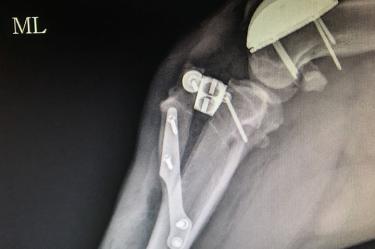

Para mejorar la calidad de vida de los perros con condiciones ortopédicas, especialistas del Hospital Veterinario de la Universidad del Valle de México ya colocan prótesis de titanio de origen suizo, un procedimiento avanzado que pocas instituciones realizan en Latinoamérica.

El especialista en ortopedia de esta institución, Beremiz Sánchez Salazar, explicó que las prótesis de titanio de última generación que utilizan son de un desarrollo suizo para reemplazar de manera parcial la rodilla en perros con degeneración articular y para su colocación se requiere que los médicos veterinarios reciban un entrenamiento específico.

También presentaba ruptura del ligamento cruzado craneal, condición muy común en caso de luxación patelar y que predispuso a una mayor inestabilidad e inflamación articular, por lo que el procedimiento a efectuarse era colocar un surco protésico para mejorar su condición biomecánica y contrarrestar el dolor.

Se reemplazó el surco degenerado por una prótesis de titanio extra pulido o ultra pulido. Esta prótesis lo que busca es tener una superficie articular sumamente lisa para evitar que haya un roce inadecuado entre la rótula y la superficie articular degenerada”, detalló el especialista, en un comunicado difundido por la UVM.